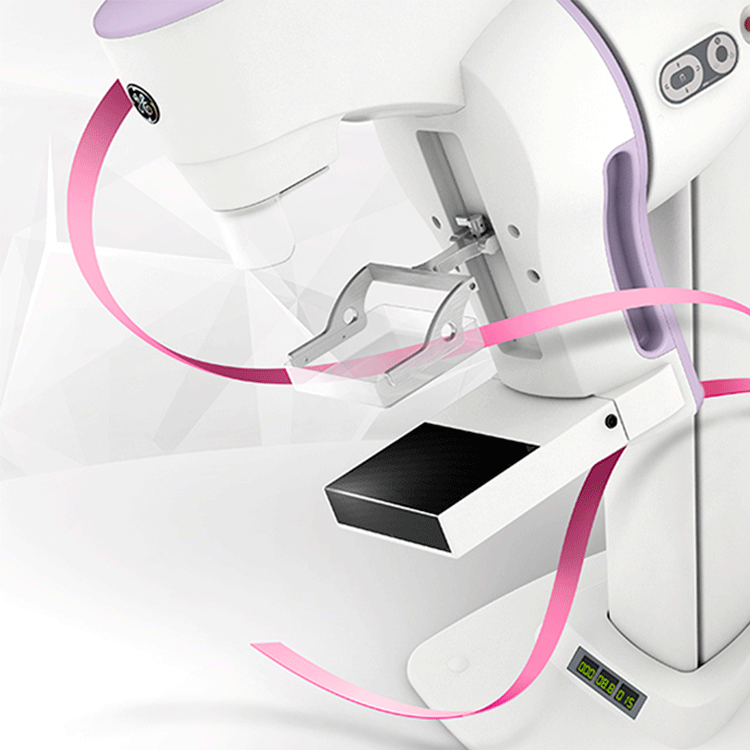

Современные маммографы Brestige: фотографии и отзывы